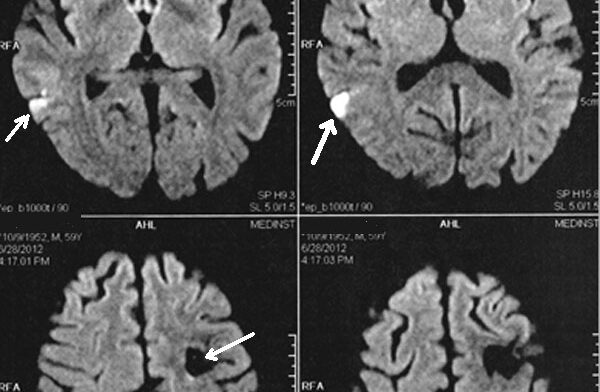

Un bebeluş din judeţul Botoşani a murit după ce ar fi fost "zgâlţâit" prea tare. Fetiţa de 6 luni a suferit grave leziuni la creier, după cum arată primele date ale medicilor legişti. Deocamdată, anchetatorii fac cercetări in rem, dar mama copilului şi prietenul acesteia sunt suspecţii principali.